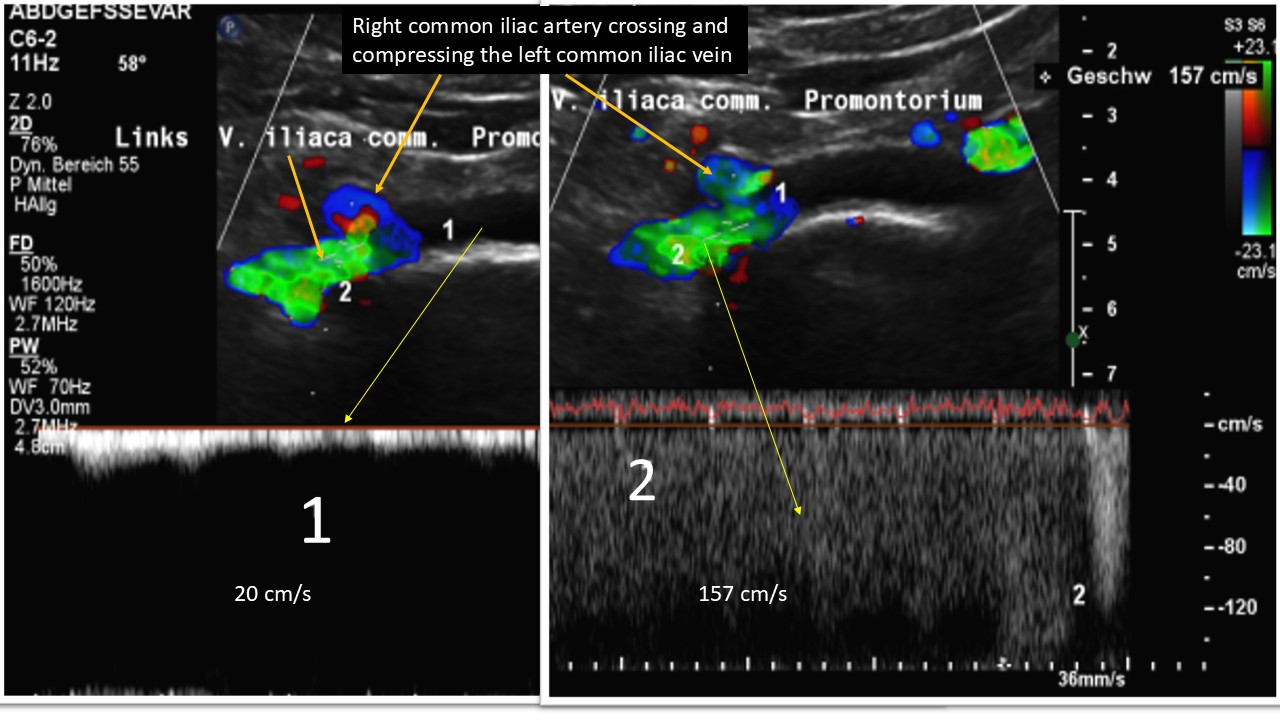

Further upstream the next outflow obstruction from the left leg is a May-Thurner syndrome due to a severe compression of the left common iliac vein:

The subsequent congestion of the pelvic circulation was massively aggravated by a left renal vein compression which pours large amounts of blood towards the pelvic circulation via its collaterals-mainly the left ovarian vein. Due to the obstruction of the pelvic outflow the additional large left renal collateral flow volume is massively affecting the outflow from the left leg thus fuelling the chronic regional pain syndrome there.

The exaggerated lumbar lordosis was compressing the inferior vena cava, which increased the backflow pressure in the left leg.